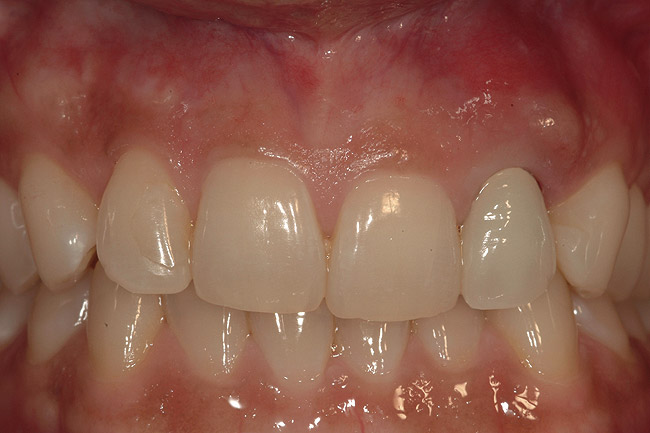

Figure 12  Postoperative clinical photograph revealed maintenance of the gingival architecture and esthetic outcomes.

Figure 12

In the present case, a submarginal incision was made at the mucogingival gingival junction, revealing the facial fenestration defect (Figure 10 ). The mucosa was elevated to access and graft both the socket and fenestration defect. Both sites were protected by a collagen membrane (Bio-Gide®), and sutured to close the submarginal incision (Figure 11 ). Medical cyanoacrylate was placed over the socket wound to stabilize the collagen membrane. Healing was uneventful, and the soft-tissue contours suggested preservation of the alveolar contours at the time of extraction. Five months after extraction and augmentation, the findings from a clinical postoperative radiograph demonstrated evidence of notable graft containment as reflected by the overall radiopacity of the extraction site, even coronal to the socket. The site was reentered for implant placement. Flap elevation revealed the dense bone ridge with complete incorporation of the particulate graft material. The osteotomy for implant placement was prepared with a trephine bur, and the resulting specimen was submitted for histologic evaluation. The histologic findings revealed evidence of robust osteogenesis throughout the bone core, including the coronal aspect supporting the soft tissue. New bone was found in close amalgamation with the FDBA-graft particles throughout the specimen. A dental implant was placed at the site in a single-stage surgery and allowed to heal for 5 months prior to the restoration. The esthetic outcome was highly acceptable, with preservation of the marginal and papillary gingiva contours (Figure 12 ). The radiographic findings showed consistent normal bone remodeling and implant integration (Figure 13 ).